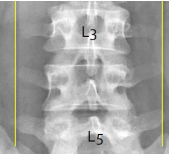

Q what is the name of this measurement? and what is the average + range?

A: Length of Lx Transverse Processes

assesses the length of the lumbar transverse processes from a line drawn through the tips of the L3 TPs. L5 should sit between these lines